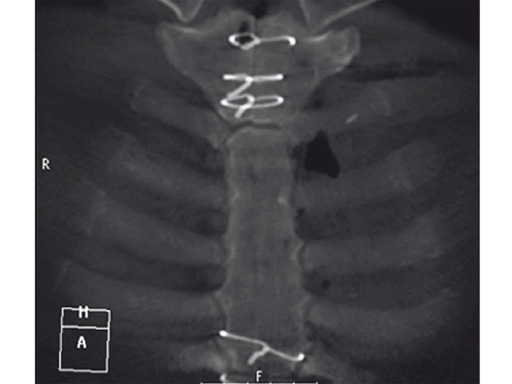

The sternal zipfix system primarily consists of polyetheretherketone (PEEK), biocompatible implants, which are similar to cable ties, and an application instrument. The purpose of this system is to achieve sternal closure following sternotomy by stabilizing the sternum and promoting fusion.

The implant itself comprises a removable stainless steel needle for peristernal application, the body with a ratchet mechanism, and a flat locking head. The application instrument is used to tension the implant, without overtensioning it, and also to cut it.

Case 2: A 55-year-old woman, who previously underwent ventricular septal defect closure at 5 and aortic valve reconstruction at 31, required aortic valve replacement due to symptomatic aortic valve insufficiency.

The patient was morbidly obese with a BMI of 45. Due to the high risk for sternal instability and/or deep sternal wound infection, closure was performed using the sternal zipfix system. The zipfix provides quick and reliable stable fixation of the sternum even in patients that are at a higher risk to develop a sternal instability or a deep sternal wound infection.

The postoperative course was uneventful and the patient was discharged on postoperative day 7 with no signs of sternal instability or wound healing problems. At 18 months follow-up the wound had healed completely and the sternum was stable, with no signs of infection.